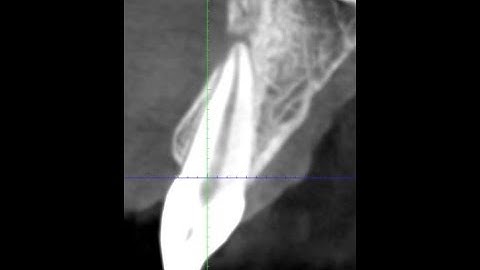

MTA apical plug(apexification)